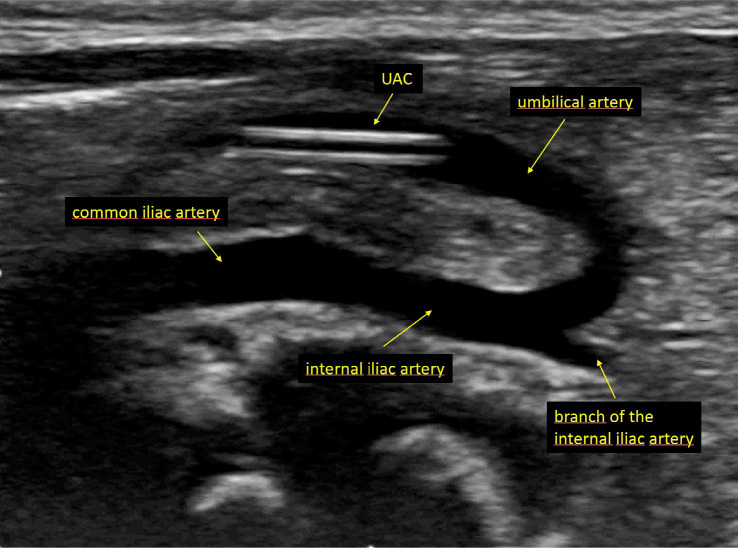

Objective: Thrombosis is a common complication of umbilical artery catheterization. The purpose of this study was to compare the novel ultralow umbilical artery catheter position (catheter tip at the junction of the umbilical and internal iliac arteries) versus the conventional high umbilical artery catheter position (tip in the aorta, above the diaphragm) for the incidence of thrombosis.

Study design: This study was conducted in a nonacademic, tertiary-referral neonatal center. The insertion and placement of the umbilical artery catheter was performed under continuous ultrasound guidance. Serial ultrasound examinations were performed to identify thrombosis in 38 consecutive newborns with an umbilical artery catheter placed in the novel ultralow position. The control group consisted of 50 infants with an umbilical artery catheter placed in the standard position.